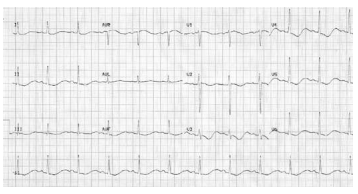

Um paciente de 68 anos de idade estava com insuficiência

cardíaca descompensada perfil B e pneumonia associada,

em uso de nitrato, hidralazina, carvedilol e furosemida ev.

Após 48 horas, apresentou fraqueza muscular, parestesias

e o ECG a seguir.

Com base nesse caso clínico hipotético, assinale a opção que apresenta o distúrbio hidroeletrolítico associado a esse quadro.

Com base nesse caso clínico hipotético, assinale a opção que apresenta o distúrbio hidroeletrolítico associado a esse quadro.